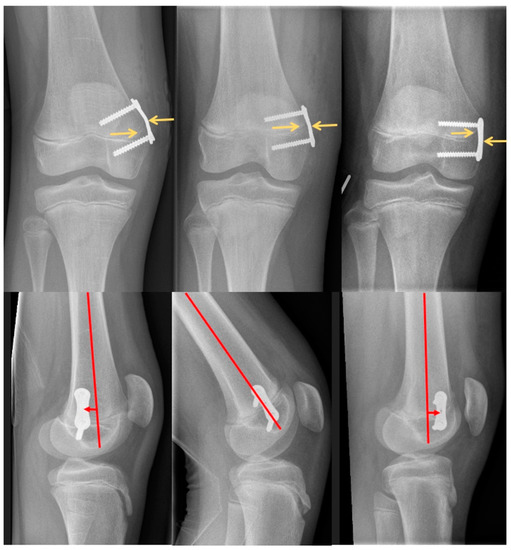

2.2. Radiographic Measurements

| Plate position in relation to the physis | 0.049 | ||

| centered | 28 (77.7%) | 14 (77.8%) | |

| epiphyseal | 6 (16.7%) | 0 (0.0%) | |

| metaphyseal | 2 (5.6%) | 4 (22.2%) | |

| Plate position in relation to the shaft axis of femur/tibia (°) | 2.1 (11.2) | 5.9 (13.5) | 0.31 |

| Plate position in relation to the center of the shaft axis of femur/tibia | 0.39 | ||

| centered | 18 (50.0%) | 10 (71.4%) | |

| posterior | 12 (33.3%) | 2 (14.3%) | |

| anterior | 6 (16.7%) | 2 (14.3%) | |

| Angulation of the two screws (°) | 0.9 (5.3) | 2.8 (6.3) | 0.26 |